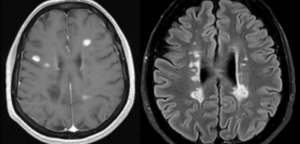

En l’apartat de la web, Documents d’Utilitat per a la consulta es troben disponibles dos documents amb instruccions per a l’enviament de mostres a la Unitat de Neuroinmunología-CSUREM de l’Hospital La Fe, referent a l’estudi d’Ac-Anti MOG, i per a la quantificació d’Atròfia Cerebral per mitjà de RM.